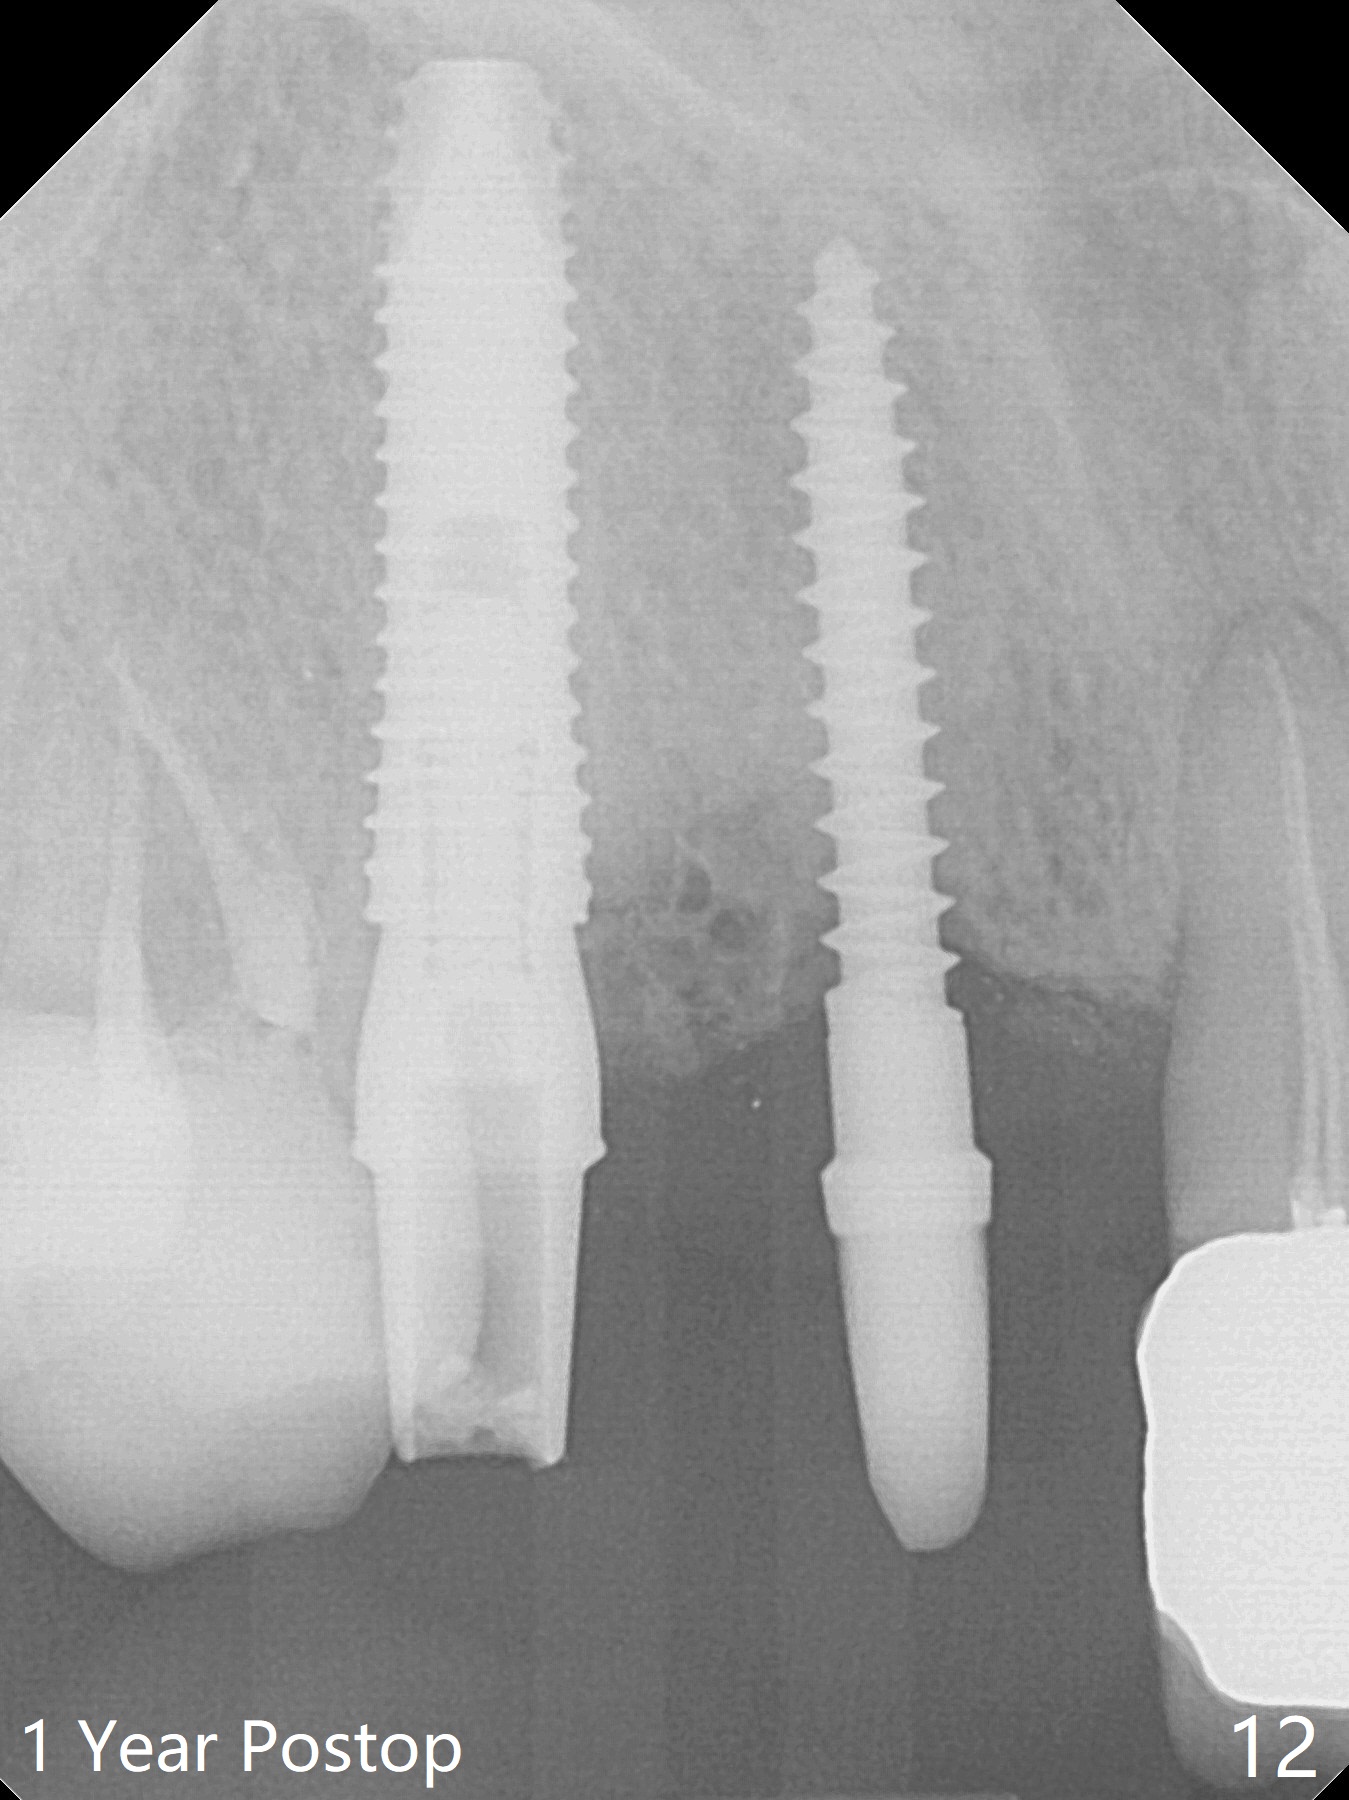

When the bridge is sectioned between #7 and 8, the tooth #6 is found non-salvageable (Fig.1).  Incision shows the atrophic buccal plate at #7 (Fig.2 arrowheads); to prevent the same feature from happening at #6 with thin buccal plate, the most buccal portion of the root is preserved (socket shield (Fig.2-4: *)).  The initial osteotomy is established in the palatal slope at #6 (Fig.5 circle) with 1.5 mm drill (Fig.6,7).  A portion of the root is visible in Fig.6 (arrowheads).  After sequential osteotomy with 2 mm, 3 mm (Fig.8) and 3.2 mm drills, a 4x15 mm implant is placed (Fig.10).  To accommodate the cross bite, the coronal portion of the implant (Fig.9 white circle) is positioned close to the socket shield.  It appears that the shield prevents the implant from encroaching the buccal plate.

Since the ridge at #7 is ~ 4 mm, a 2.5x14 mm 1-piece implant is placed (Fig.8) after 1.2 mm (Fig.7), and 1.5 mm drills at 12 mm and 2 mm drill at 8 mm.  Later the implant is placed deeper (Fig.10).  There is no bone loss 7 or 12 months postop, respectively (Fig.11,12).  After Diode gingivectomy, there is papillary formation (Fig.13).  No provisional is provided after impression (with the abutment torqued at #6) for oral hygiene.  With access holes at #6 and 7, crowns are bonded with minimal residual cement (Fig.14 <, which is removed later).  There is no hard (Fig.15,16) or soft (Fig.17 *) atrophy 26 months postop, i.e., 13 months post cementation, due to the presence of socket shield (Fig.15 <, as compared to Fig.1).  In fact the tooth #8 has mobility and fremitus (short root/poor crown/root ratio, Fig.16); occlusal adjustment is done 13 months post cementation.  The crown is dislodged 2 years 1 month post cementation; a prefabricated post is being tried in (Fig.18).  There is no atrophy, bone loss or infection at #6 (with socket sheath (*)) or 7 two years 5 months post cementation (Fig.20-27).